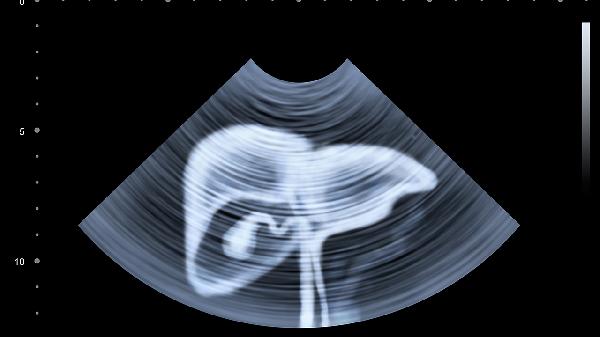

肝脏代谢胆红素障碍时会导致黄疸,表现为巩膜和全身皮肤发黄,可能伴随皮肤瘙痒。这种情况常见于急性肝炎、胆管梗阻等疾病,需通过肝功能检测和腹部超声明确病因。治疗可选用茵栀黄颗粒、熊去氧胆酸片等药物,同时需限制高脂饮食。

右上腹持续隐痛或胀满感可能与肝脏肿大相关,常见于脂肪肝、肝囊肿等疾病。疼痛可能放射至右肩背部,进食油腻食物后加重。建议完善CT或弹性成像检查,可遵医嘱使用复方甘草酸苷片、水飞蓟宾胶囊等护肝药物,日常需戒酒并控制体重。